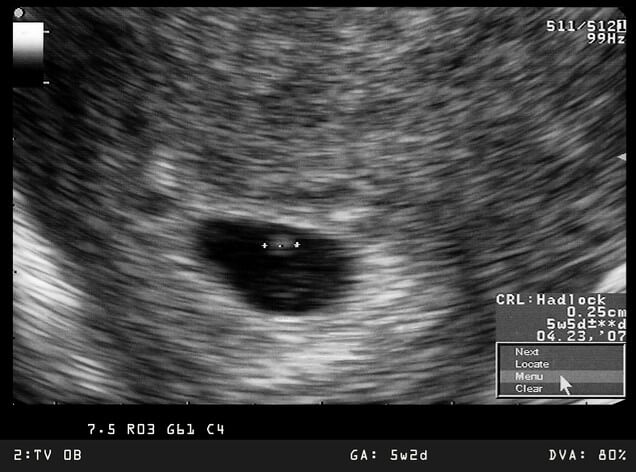

พัฒนาการทารกในครรภ์สัปดาห์ที่ 5-8

“แม่จ๋า หัวใจหนูเต้นแล้ว”

• ขนาดของทารก: ตัวอ่อนในครรภ์จะมีความยาวประมาณ 4 - 25 มิลลิเมตร รูปร่างโค้งงอ

• การตั้งครรภ์ยังไม่สามารถสังเกตเห็นได้ชัด

• ตัวอ่อนเริ่มพัฒนาอวัยวะสำคัญ เช่น หัวใจ ระบบประสาท ตา แขนและขา

• ตรวจพบการเต้นของหัวใจของตัวอ่อนในครรภ์ช่วงอายุครรภ์ตั้งแต่ 6 สัปดาห์ขึ้นไป จากการทำอัลตราซาวนด์ทางช่องคลอดได้ด้วยเครื่องตรวจคลื่นเสียงความถี่สูง